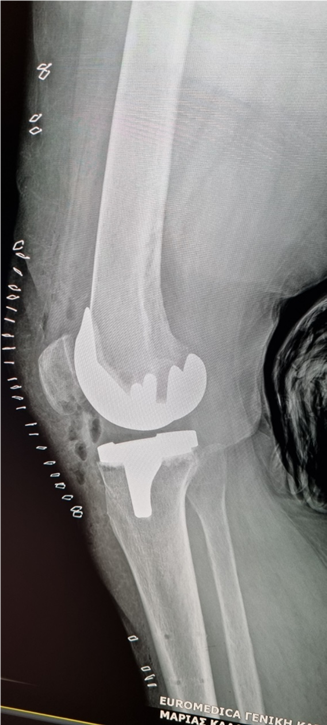

- Αποτέλεσμα: Ιδανική ανατομική και λειτουργική τοποθέτηση της πρόθεσης, με επιβεβαίωση σε πραγματικό χρόνο και μετεγχειρητική ακτινογραφική τεκμηρίωση της σωστής ευθυγράμμισης.

Μετεμφυτευτική αναπαράσταση και επιβεβαίωση της άριστης ανατομικά, αλλά και βιομηχανικά τοποθέτηση της νέας άρθρωσης

Μετεγχειρητική ακτινογραφία